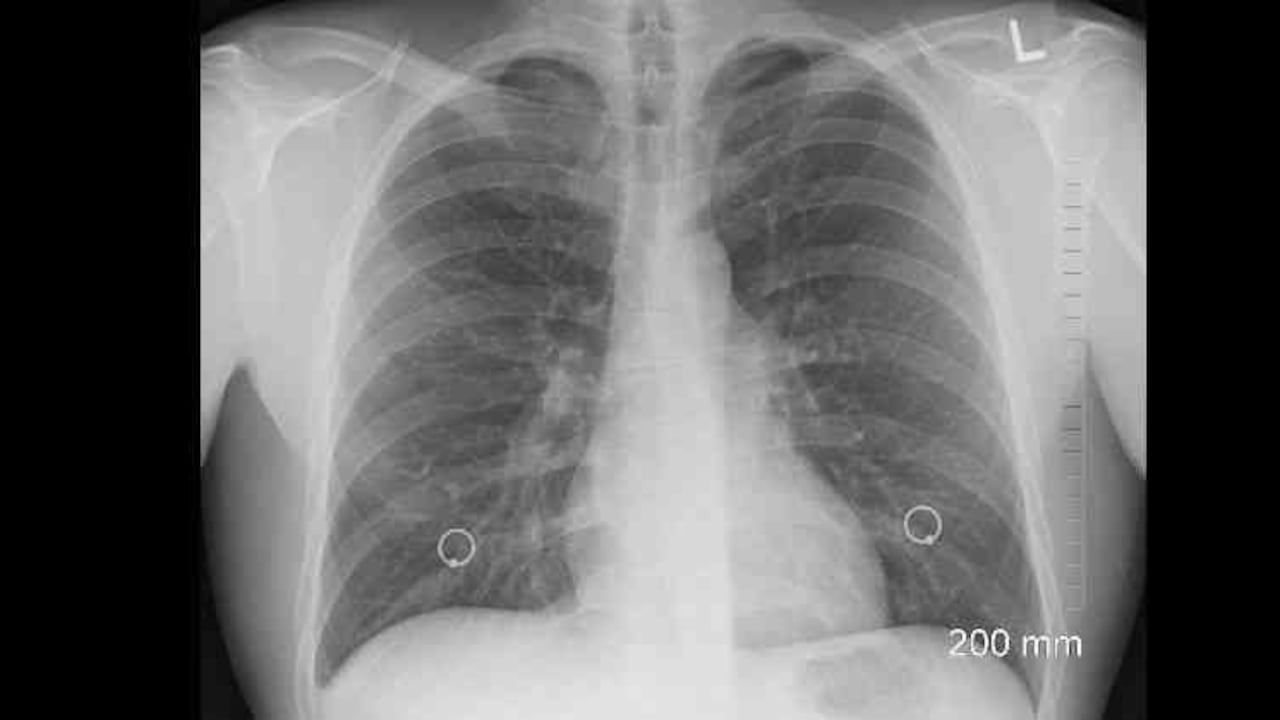

En el diagnóstico del cáncer pulmonar hay etapas preinvasivas que no se consideran cáncer aún. También hay displasias, es decir, cuando las células están creciendo irregularmente sin ser todavía tumorales. Hay hiperplasias que es hipercrecimiento. Encontrar las lesiones preinvasivas es muy importante para nosotros los médicos. Lo ideal es identificarlos con un nódulo, hacerles endoscopia y si es así se hacen dos cosas: seguir observándolos cada tres meses y luego cada año o, si hay mérito, sacar el nódulo para estar tranquilos. Pero cuando la persona tiene síntomas es porque las cosas han avanzado y en esas circunstancias es más difícil el tratamiento. Por eso, de 10 pacientes con cáncer de pulmón, a 1 o máximo 2 en ciertos niveles tempranos se les puede ofrecer un tratamiento curativo. A los otros 8 o 9 que están en estados avanzados no se les puede dar porque llegaron tarde debido a la falta de sintomatología. Además, los fumadores pesados de más de 45 años, que son de alto riesgo, no se hacen exámenes para detectar anomalías.